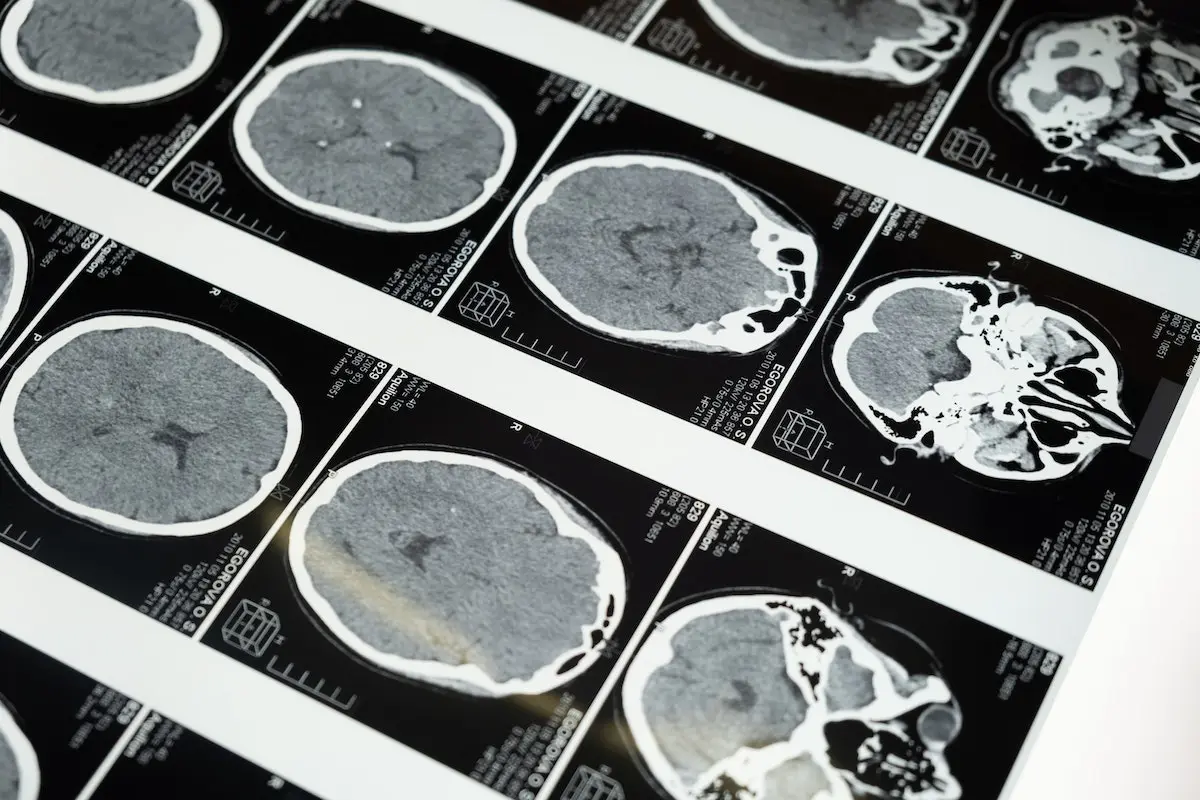

For individuals grappling with various brain and nerve issues such as autism, concussion, traumatic brain injury (TBI), post-traumatic stress disorder (PTSD), attention deficit hyperactivity disorder (ADHD), pain, and more, hope comes in the form of neurofeedback—a well-established brain coordination technology. When paired with Hyperbaric Oxygen Therapy (HBOT), neurofeedback can potentially supercharge the healing process. This powerful duo could be the key to unlocking better results for individuals seeking relief from a range of neurological challenges.

Oxygen as a Catalyst for Brain Restoration

The magic of oxygen sets the stage for brain restoration. Bathing cells in a rich supply of oxygen provides them with the regenerative fuel necessary for building new tissue. This includes nerves, synapses, stem cells, and more. Pressurized oxygen creates an ideal environment for genuine repair to take place. In parallel, neurofeedback actively trains the brain to perform at its best. Think of neurofeedback as a workout for your brain “muscles.” It rapidly teaches the brain to reorganize itself through precise training, enabling pathways to reassemble into a more efficiently coordinated unit. While HBOT optimizes the environment for physical restructuring, neurofeedback enhances brain performance, thereby unlocking tremendous healing potential.